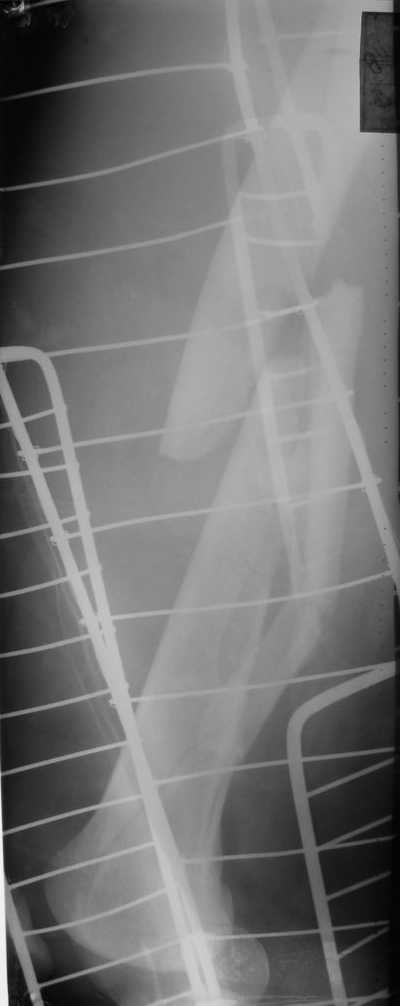

Уважаемые коллеги! Поступил пациент 46 лет после автоаварии от 3.01.

Лечился в ЦРБ. К нам поступил вчера. Имеется оскольчатый перелом диафиза левого бедра, перелом медиального мыщелка, краевой перелом надколенника. У нас, кроме того, выявили перелом шейки бедра. Перелом закрытый, имеется рана в в/3 голени(ниже уровня бугристости б/берцовой кости)без признаков инфицирования.Планируем закрыто фиксировать мыщелок и надколенник винтами, затем закрыто заштифтовать бедро. Вопрос возник по перелому шейки: что предпочесть - длинный PFN или DFN + DHS на шейку?Буду благодарен за ценные советы.С уважением, Станислав Дмитриев.

Заранее приношу извинения за качество снимков. То что есть - либо из ЦРБ, либо сделано в приемном покое, где дежурят рентгенлаборанты различной квалификации. Завтра постараемся сделать снимки всего бедра на длинные кассеты в 2 проекциях. Сейчас больной на скелетном вытяжении. Состояние стабильное.